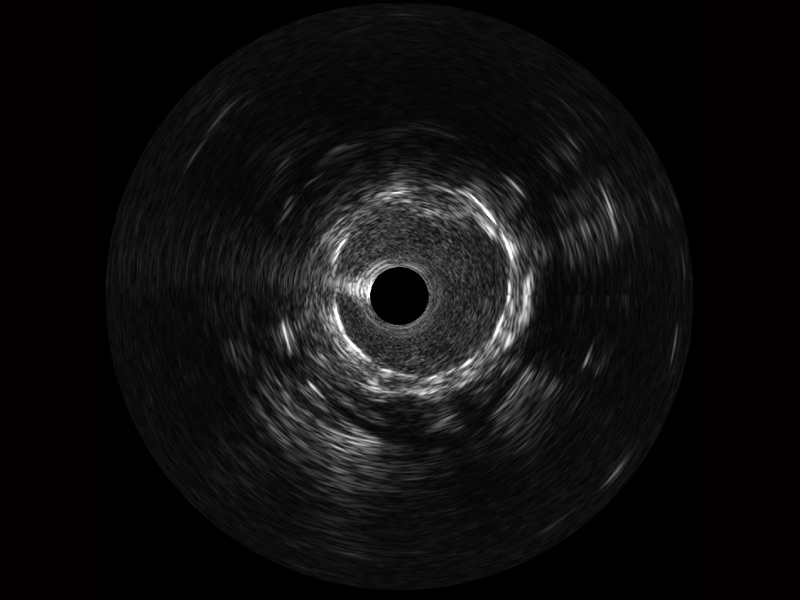

• 传统IVUS图像

对比传统IVUS导管成像,百老汇电子游戏官网宽频IVUS图像的近场支架梁显影更细腻,远场中膜外血管仍清晰可辨,兼顾远中近,兼顾分辨力与穿透深度